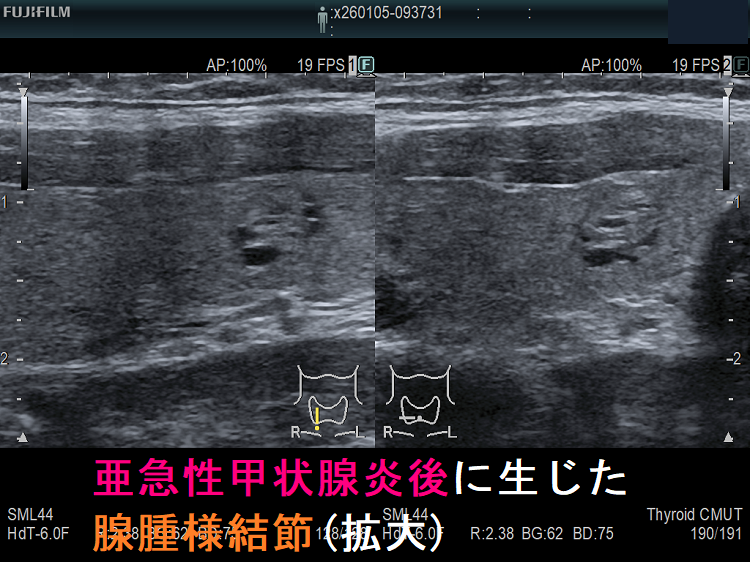

上記のようにならなくても、亜急性甲状腺炎で甲状腺組織が破壊され、さらに代償的の組織増殖が起こると、

- のう胞変性(嚢胞変性);甲状腺組織が溶けてしまい、空洞ができる

- 代償的に組織が増殖し、腺腫様結節(過形成結節)→腺腫様甲状腺腫

が生じます。長崎甲状腺クリニック(大阪)では、亜急性甲状腺炎が終息して数カ月後に、さらには年単位で甲状腺超音波(エコー)検査を施行しています。

亜急性甲状腺炎治癒後;矢印が腺腫様結節